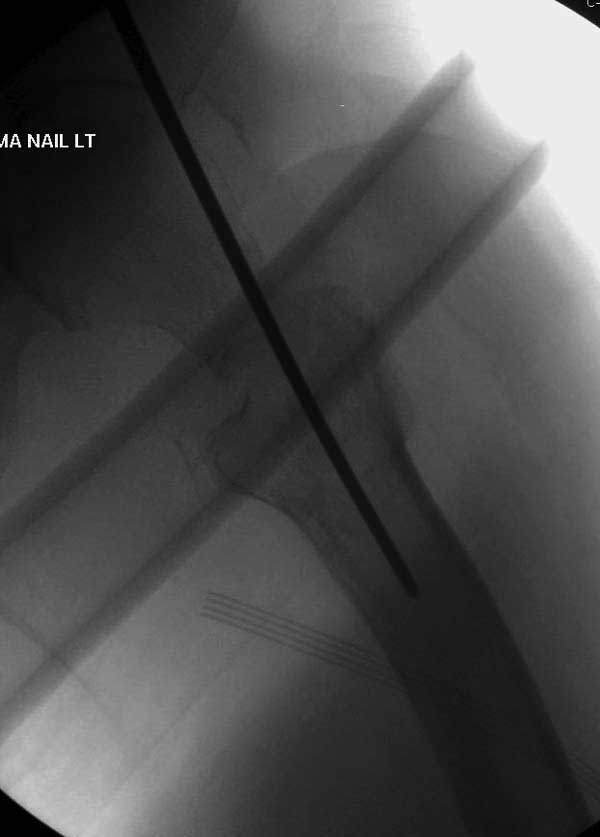

Повторно поступает после двух с половиной лет, где обнаруживается перелом на второй стороне. Немного сложно, но для фиксации выбрали Antegrade InterTan Smith Nephew Nail и с момента фиксации более 3х мес.